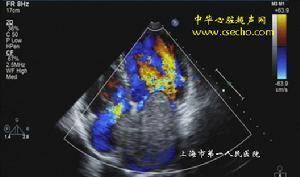

4.超聲心動圖左房粘液瘤在左心腔內見到異常的點片狀反射光團,活動於左房、左室之間,收縮期回到左房腔,舒張期達二尖瓣口進入左室,二尖瓣前葉EF斜率減低,左房增大。右房粘液瘤異常反射光團在右心腔內,收縮期在右房,舒張期隨三尖瓣向右室方向移動或通過三尖瓣口進入右室腔。右房、右室增大。

3.超聲心動圖檢查顯示瘤體隨心臟收縮和舒張活動。心血管造影顯示心腔內占位性病變,但有一定的假陽性、自有超聲心動圖,心血管造影較少套用。